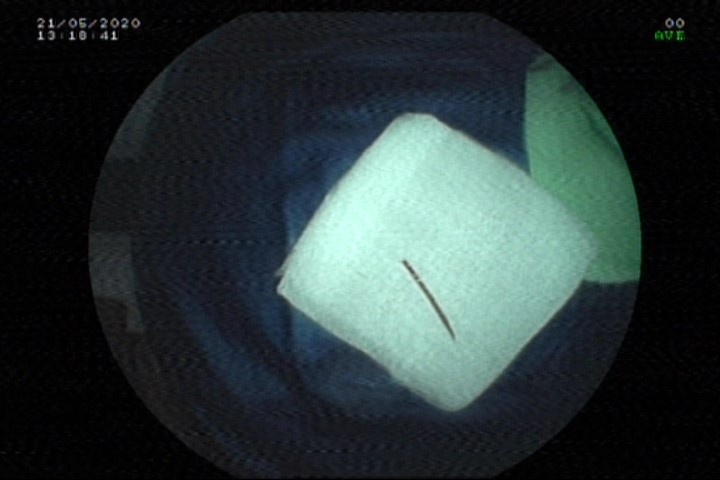

Đoạn tăm dài 2 cm được bệnh viện gắp thành công. Ảnh: Bệnh viện cung cấp.

Bác sĩ Lý Thanh Thư, Khoa Nội tiêu hóa - Gan mật - Nội tiết, Bệnh viện Hoàn Mỹ Đà Nẵng, cho biết sau khi nội soi, bác sĩ đã lấy ra dị vật là một đoạn tăm tre dài 2 cm. Trong đó, một đầu nhọn tăm tre đâm vào ống hậu môn, đầu còn lại trong lòng trực tràng.